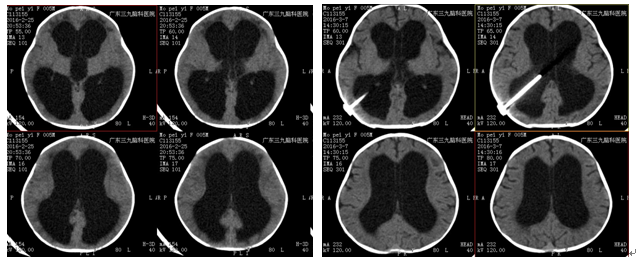

治疗:在全麻下行脑室腹腔分流术治疗,术中成功置入可调压式脑室腹腔分流管。术后给予抗感染、补液、营养脑细胞对症治疗。定期复查头颅CT了解脑积液的引流情况,观察病情变化。

术前MRI 术后MRI(受压脑实质,明显恢复)